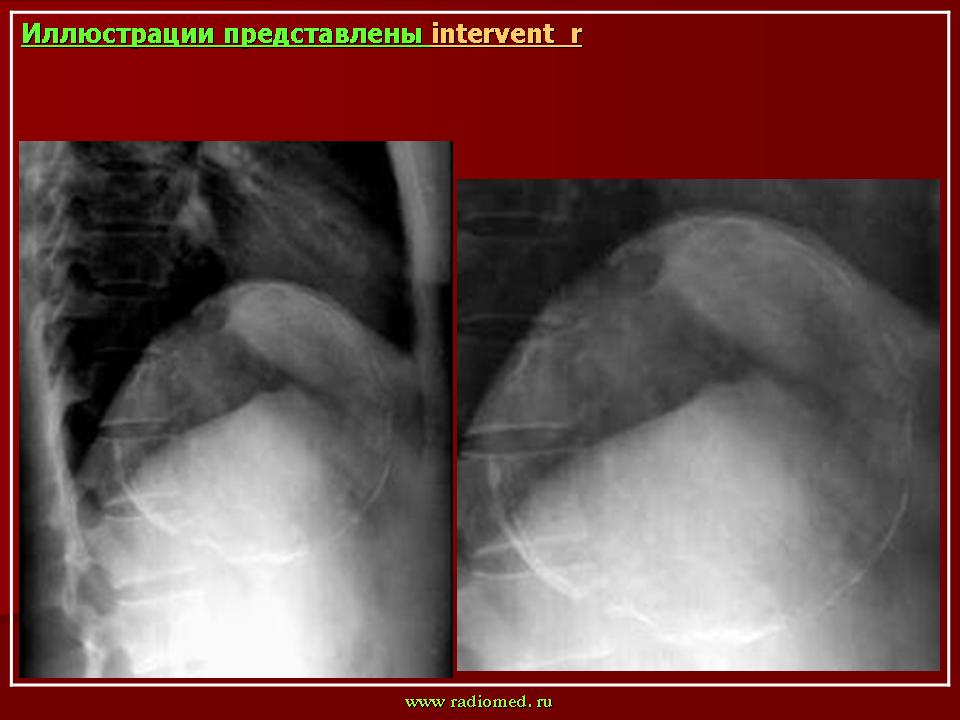

Э в виде простой кисты наблюдался у 6 больных и был вторым по частоте встречаемости - при ультразвуковом исследовании в одном из сегментов печени выявлялось анэхогенное образование размерами от 3 до 5 см. Высказать предположение о паразитарном характере образования удалось у 4 пациентов.В 1 случае внутри кистозного образования выявлялась эхогенная взвесь, симптом “снежной бури”, еще в одном на возможный Э указывало наличие двухслойной капсулы, и у 2 пациентов имелось сочетание внутренней взвеси и толстой капсулы. У 2 пациентов киста не отличалась от простой солидной кисты печени, однако, учитывая эндемичность района по Э, работа связанная с уходом за животными, были проведены серологические реакции, оказавшиеся положительными на Э. Оперативное вмешательство подтвердило диагноз. На третьем месте по частоте было выявление в печени полукольца обизвестления (4 больных) - дугообразной линии гиперэхогенного сигнала с анэхогенной зоной дистальнее, толшина полукольца колебалась от 1,4 до 2мм (рис 2).